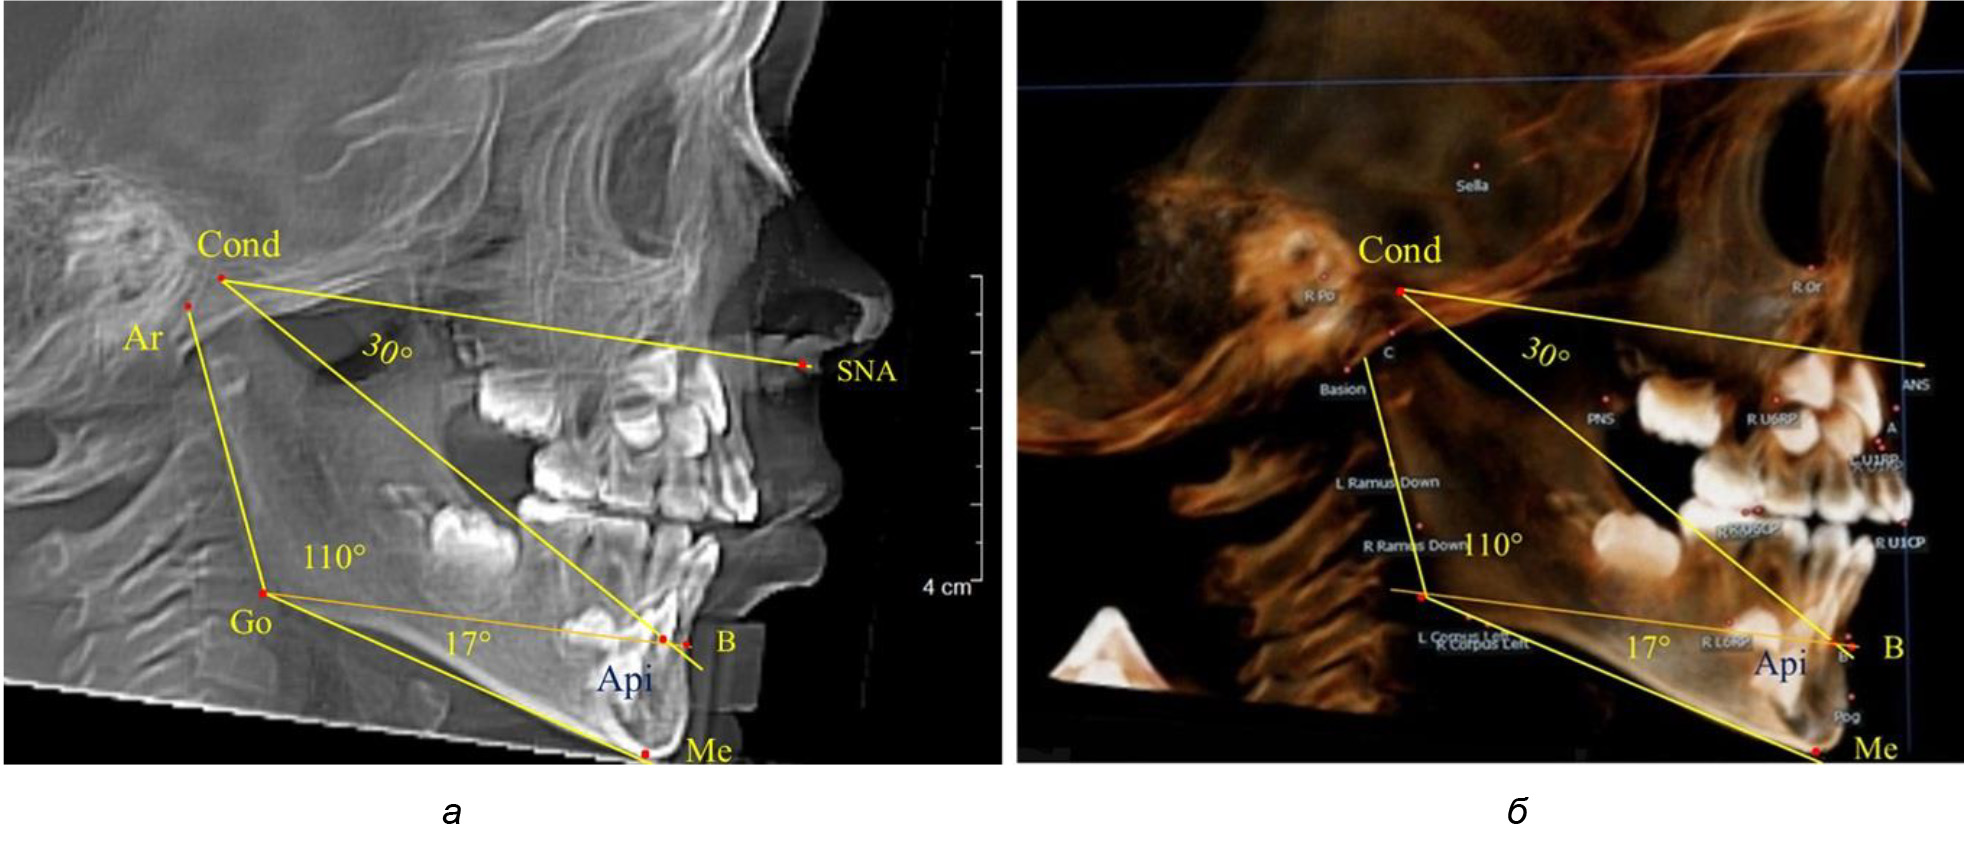

После смены всех молочных зубов (анализ 9 ТРГ) и после прорезывания вторых постоянных моляров (7 человек) происходил очередной этап подъема высоты прикуса с увеличением размеров костей гнатической части лица. Однако величина основного угла гнатической части лица SNA-Cond-Api, так же как в молочном и сменном прикусе, в норме составляла (30,02 ± 1,25)°, что не имело достоверных различий (р ˃ 0,05) с аналогичным параметром, анализируемом в других группах исследования. Угол нижней челюсти и его составляющие отличались вариабельностью параметров при различных показателях нижнечелюстного угла (рис. 6).

Рис. 6. Варианты 3D рентгенограмм детей после смены всех молочных зубов (а) и после прорезывания вторых моляров (б)

Таким образом, данные, полученные при исследовании детей с физиологическим прикусом в различные периоды онтогенеза, показали, что величина основного угла гнатической части лица SNA-Cond-Api была относительно стабильным параметром, вне зависимости от линейных параметров челюстных костей. Данный показатель может служить ориентиром для дифференциальной диагностики зубоальвеолярных и гнатических форм аномалий окклюзии в вертикальном направлении.

При анализе 16 рентгенограмм с аномалиями окклюзии в вертикальном направлении были выявлены признаки изменения основного гнатического угла. Так, для гнатических аномалий глубокой резцовой окклюзии/дизокклюзии (9 человек) отмечалось уменьшение угла гнатической части лица, величина которого была менее 26°. В то же время для гнатических аномалий (7 человек) вертикальной резцовой дизокклюзии («открытый» прикус) определялось увеличение угла гнатической части лица, который превышал значения в 33° (рис. 7).

Рис. 7. Варианты ТРГ при глубоком прикусе (а) и при открытом прикусе (б)

На представленных клинических примерах, несмотря на различия параметров основного угла гнатической части лица, определялись однотипные варианты угла нижней челюсти Ar-Go-Me и его составных частей Ar-Go-Api и Api-Go-Me.

Таким образом, установлено, что основным показателем, определяющим оптимальные параметры гнатического отдела лица, является угол гнатического отдела лица, образованный пересечением линии, соединяющей точку передней носовой ости с верхней точкой суставной головки SNA-Cond, и линией, отходящей от суставной точки до верхушки корня нижнего медиального резца Cond-Api. Средняя величина угла гнатического отдела SNA-Cond-Api составляла (29,96 ± 0,84)° при физиологической окклюзии постоянных зубов и практически была аналогичной во все периоды онтогенеза.